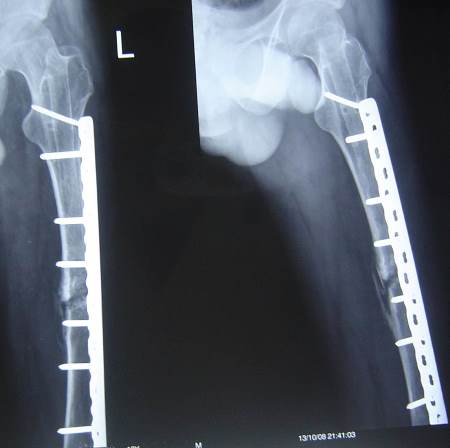

Nail or plate?

Operative time: 4 hours nail removal + 2 hours plate insertion.

Blood loss: 2000cc, 3 units transfused.

Middle part of the nail was removed by a small break in the lateral cortex.

Distal part of the nail was removed by a hole distally in the lateral cortex then pushed by a drill pit and pulled through the medulla by an intestinal clamp.

Bone graft.